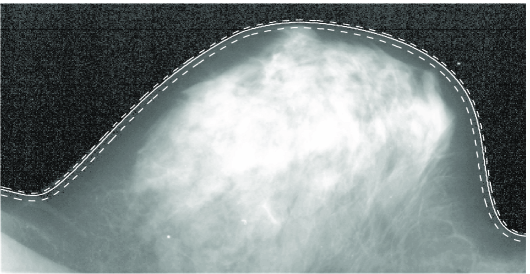

We next consider an example of boundary reconstruction in mammography, where the skin-air contour is used to determine the radiographic density of the tissue and to estimate breast asymmetry. Both measures are known to be associated with the risk of developing breast cancer (Scutt et al., 1997; Ding et al., 2008). In Stanberry and Besag (2009), B-spline curves were used to reconstruct a smooth connected boundary of an object in a noisy image, and a Bayesian approach was applied to estimate the tissue boundary in mammograms.

The boundary reconstruction was performed on a binary image which was obtained after filtering and thresholding the original greyscale mammogram. Let be the compact domain of the mammogram image, and let denote the random set describing the breast tissue, or foreground, of the image under the prior belief distribution. Next, let denote the noisy binary mammogram image observed. The skin-air boundary estimate is reconstructed as , the expected boundary of from the posterior distribution given the observed data . The posterior distribution of the random set is too difficult to compute, and was approximated via Markov chain Monte Carlo. Hence, the skin-air boundary estimate was also approximated as from a sub-sample of observed random sets generated from the MCMC simulation. Further details can be found in Stanberry and Besag (2009). Here, we apply the proposed method to construct a confidence region for the posterior mean boundary. We emphasize that the confidence region is not a credible set, but rather it describes the variability of as an estimator of

Figure 10 (left) shows a typical digitized mammogram image, characterised by a low contrast-to-noise ratio. A probability integral transform improves the contrast by increasing the dynamic range of image intensities (Figure 10, centre). The solid white line in Figure 10 (centre and insets on right) shows the reconstructed boundary Note that what appears to be a nipple is, in fact, a duct system leading to the nipple, so that the estimators correctly follow the skin line.

The 95% confidence set (dashed) for the true boundary in Figure 10 is obtained using a bootstrap resampling of size 1000. The confidence set is tight and fits the image well. It also shows that the reconstructed boundary is more variable toward the inside of the breast tissue. The background of the black and white mammogram image has considerably more noise than the foreground. Consequently, the posterior boundary samples show more variability toward the inside of the tissue. More details can be seen in insets in Figure 10 (right).

Note also that to apply our methods, we have assumed that the observed ODFs are independent and identically distributed, whilst the boundary reconstruction is based on Markov chain Monte Carlo sampling from the posterior. To ensure the independence of the curve samples, we construct the confidence set for the boundary using 100 samples from the posterior, which were acquired every 250th sweep after a burn-in period of 1000 sweeps.